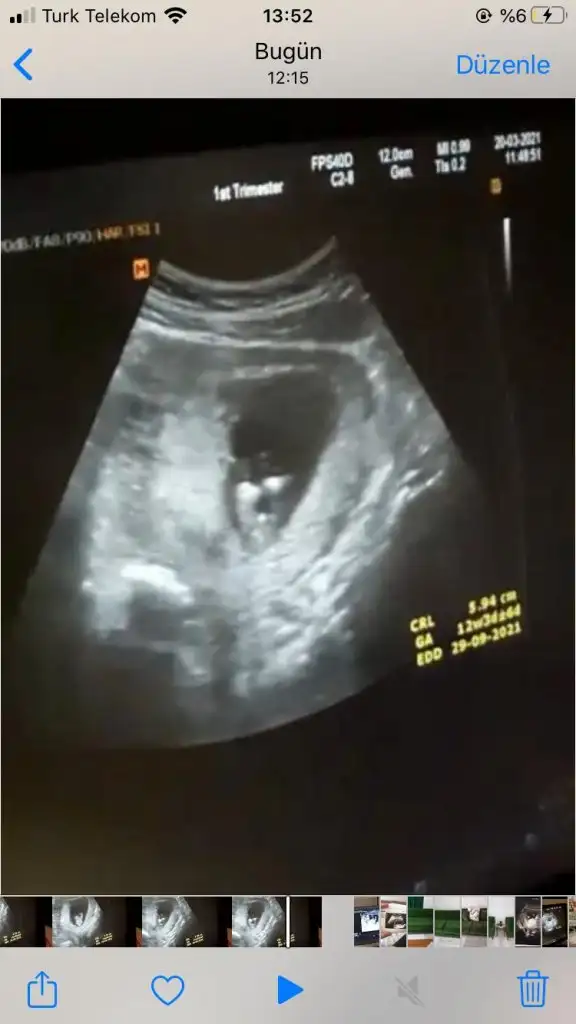

Merhabaa güzel anne aramıza hoşgeldinMerhaba herkeseben de nasipse eylül annesi olacağım. Ama inanılmaz panik halindeyim. Kimsemin olmadığı bir şehirde yalnız yaşıyorum, eşimle aramızda da çok mesafe var sık sık bir araya gelemiyoruz. İlk gebeliğim olduğu için de neyi nasıl yapmam gerektiğini bilmiyorum. Herşeyin olumsuzunu düşünüyorum. Mesela İnternette sola yatılmalı yazısını gördüğüm için sağıma yattığımda kesin olumsuz birşey oldu diye kendi kendimi yiyip bitiriyorum. Dualar ediyorum kendimi sakinleştirmeye çalışıyorum ama malesef benim gibi olanlar var mı nasıl sakinleştirebiliyorsunuz kendinizi